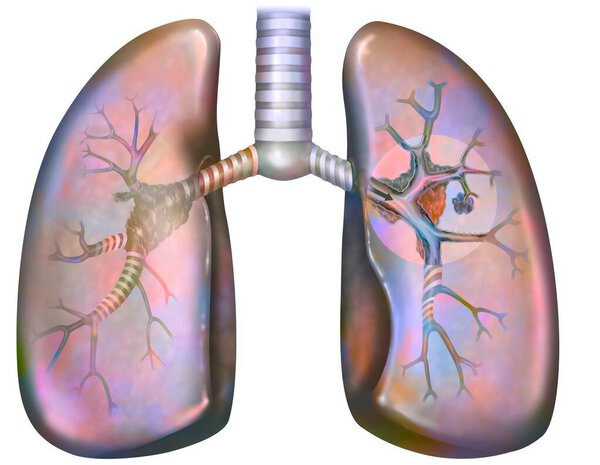

- Рак легких курильщика (с наличием депозитов смолы в бронхах).

Рак легких курильщика (с наличием депозитов смолы в бронхах).

Рак легких курильщика (с наличием депозитов смолы в бронхах).